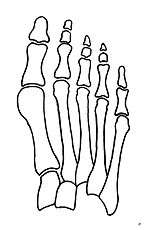

What is the metatarsus primus varus deformity?

It is leaning of the first metatarsal bone away from the second metatarsal and towards the opposite foot (Fig. 1). As it leans over, its head sticks out to form the bunion bump and it also widens the forefoot to cause shoes feeling too tight. Thus when bunion pain becomes unmanageable, surgical correction is to narrow the forefoot by repositioning of the first metatarsal head back to its normal position. This can be done by osteotomy (bone-breaking), soft tissue (non-osteotomy) or fusion techniques.